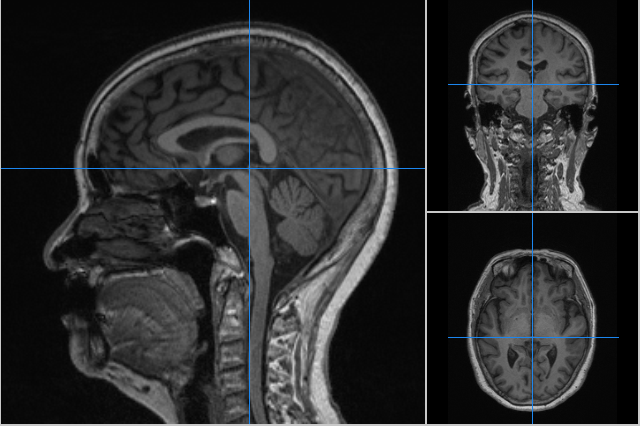

下丘脑错构瘤的mri影像表现